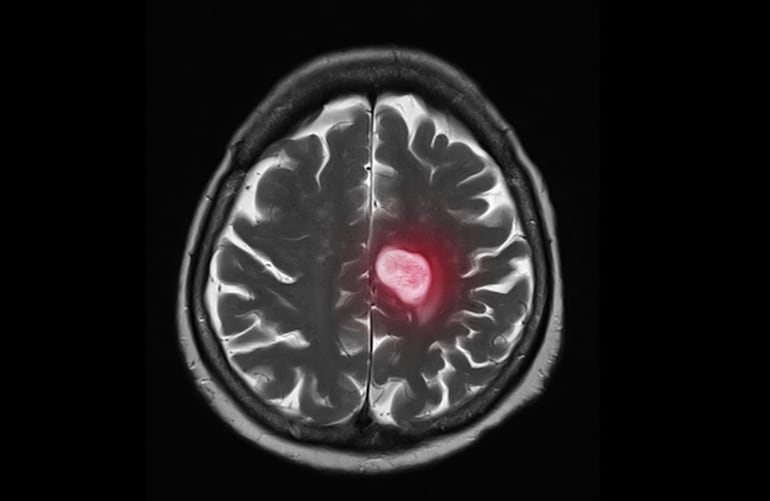

Investigadores españoles han descubierto un mecanismo por el que las células tumorales consiguen alterar el cerebro para lograr establecerse y diseminar el cáncer haciendo así metástasis, y han comprobado además que un fármaco que ya se está utilizando para otras indicaciones como el asma podría ser útil para frenar ese proceso.

Normalmente, cuando las células cancerígenas llegan al cerebro no tienen casi herramientas para sobrevivir y la mayoría son eliminadas, pero algunas sí consiguen alterar el cerebro y “secuestrar” a las células que deberían encargarse de defenderlo (los llamados macrófagos y microglía), y en lugar de combatir el tumor esas defensas son reprogramadas y trabajan a favor del cáncer.

El CNIO ha valorado la importancia del descubrimiento, ya que aproximadamente un 30 por ciento de los pacientes de cáncer (especialmente los de mama, pulmón, piel, colon y recto) acaban desarrollando metástasis en el cerebro, y actualmente es una necesidad médica no cubierta porque no hay tratamientos específicos, más allá de la radioterapia y la cirugía.